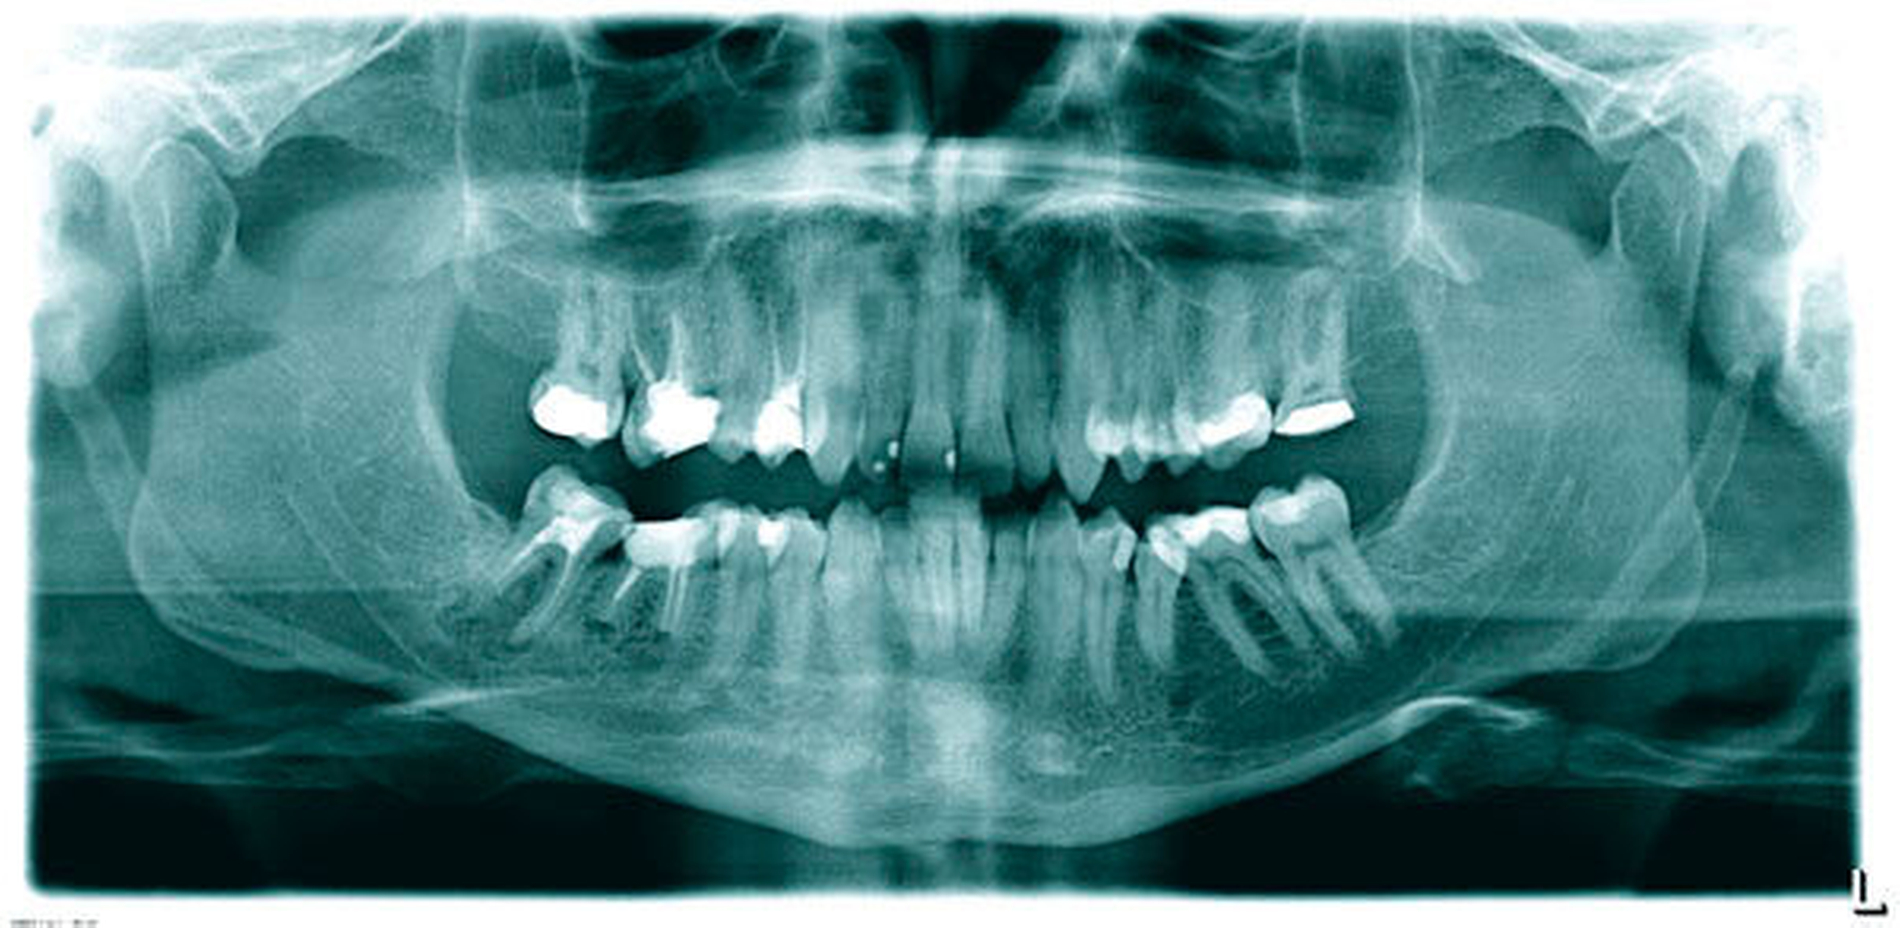

Ein 31-jähriger Patient stellte sich mit seit Monaten bestehenden Schmerzen im Unterkiefer rechts vor. Die Zähne 46 und 47 waren perkussions- und aufbissempfindlich. Es lag keine Fistel oder Schwellung vor. Distal des Zahnes 46 war ein Knochenabbau mit Ausbildung einer Tasche von 6 mm zu beobachten. Ein anderthalb Jahre altes OPTG wurde vom Patienten mitgebracht (Abbildung 9). Zusätzlich wurde eine Einzelzahnaufnahme der beiden Zähne angefertigt (Abbildung 10). Beide Zähne wiesen insuffiziente Wurzelkanalfüllungen und große apikale Läsionen auf. Die distale Wurzel des Zahnes 47 war apikal resorbiert. An Zahn 46 war vor mehr als fünf Jahren eine Wurzelspitzenresektion durchgeführt worden.

In der ersten Sitzung erfolgten die Trepanation des Zahnes 46 und die komplette Entfernung der Guttapercha unter Kofferdam (Abbildung 11). Nach ausgiebiger Desinfektion mit NaOCl 5 Prozent und EDTA 17 Prozent sowie Schallaktivierung mittels EDDY-Spitzen erfolgte eine medikamentöse Einlage mit AH Temp. In der zweiten Sitzung wurden nach der endometrischen Ermittlung der Arbeitslänge (mesiobukkal 15 mm, mesiolingual 14 mm und distal 13,5 mm) die Kanäle manuell bis ISO 70 aufbereitet. In alle drei Kanäle wurden dann apikale Plugs mit ProRoot MTA (DentsplySirona, Bensheim) eingebracht und diese radiologisch kontrolliert (Abbildung 12). Im Anschluss wurden die koronalen Kanalanteile und die Zugangskavität mit dual-härtendem Komposit verschlossen. Danach wurde die orthograde Revision an Zahn 47 durchgeführt, wobei der anresorbierte distale Kanal ebenfalls mit MTA verschlossen wurde. Abbildung 13 zeigt die Kontrollaufnahme der beiden Zähne nach der Behandlung. Die Nachkontrollen nach neun und 18 Monaten zeigen einen deutlichen Rückgang der Läsionen (Abbildungen 14 und 15) und die Zähne waren symptomfrei. Jedoch kam es zu einer Zunahme der distalen parodontalen Tasche an 46.